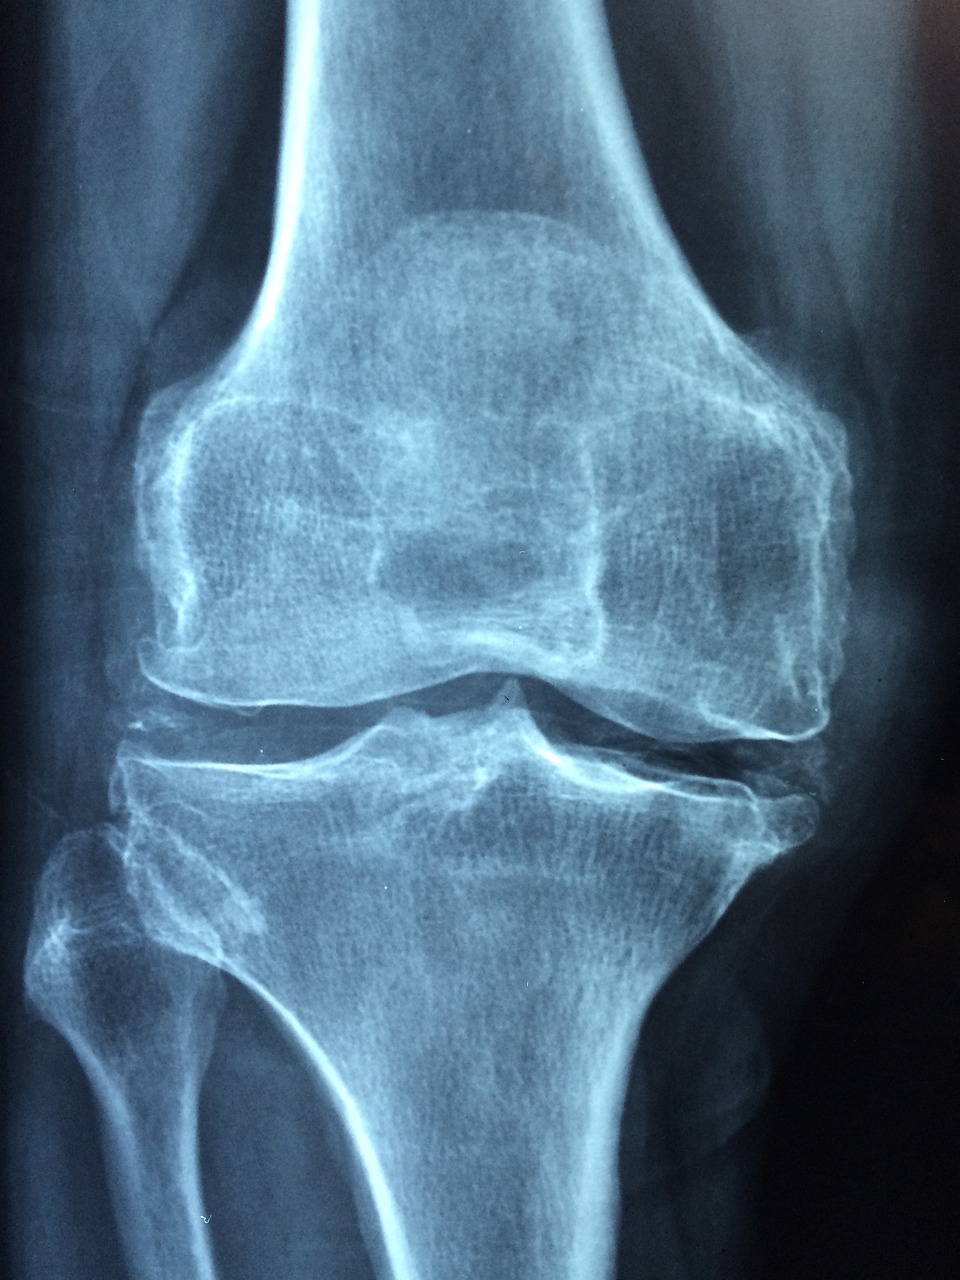

관절염은 관절에 영향을 주는 염증성 질환으로, 여러 다른 형태가 있습니다. 가장 흔한 두 종류는 오스테오아르트리티스(퇴행성 관절염)와 류마티스 관절염입니다. 관절염의 증상은 종류에 따라 다르지만, 일반적으로 다음과 같은 공통적인 증상들이 나타날 수 있습니다:

- 관절의 변형: 특히 류마티스 관절염 같은 염증성 관절염은 관절과 주변 조직의 손상으로 인해 관절이 변형되거나 비정상적인 모양을 취할 수 있습니다.

- 운동 범위 감소: 관절염이 진행됨에 따라, 관절의 운동 범위가 점차 감소할 수 있으며, 일상 생활에서의 움직임이 어려워질 수 있습니다.